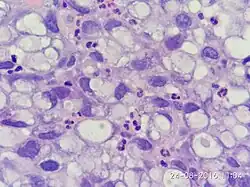

Дискогезивная карцинома (англ. poorly cohesive carcinoma) желудка (карцинома со слабым образованием межклеточных соединений) – злокачественная опухоль желудка эпителиального происхождения, для которой характерно диффузное расположение опухолевых клеток, изолированно друг от друга или в виде небольших групп.

Клетки опухоли могут иметь перстневидноклеточную цитоморфологию, то есть иметь округлую форму с эксцентрически расположенным ядром, вследствие большого количества внутриклеточного муцина. Также, они могут напоминать по своему строению лимфоциты, гистиоциты и плазматические клетки. Располагаются клетки, как правило, диффузно, могут формировать небольшие группы в виде полос железистоподобных структур с выраженной десмопластической реакцией стромы. Могут сочетаться с тубулярным и микропапиллярным видами организации опухолевой ткани.

Постановка гистологического диагноза «дискогезивная карцинома» подразумевает преобладание клеток опухоли с соответствующими характеристиками над другими патернами.